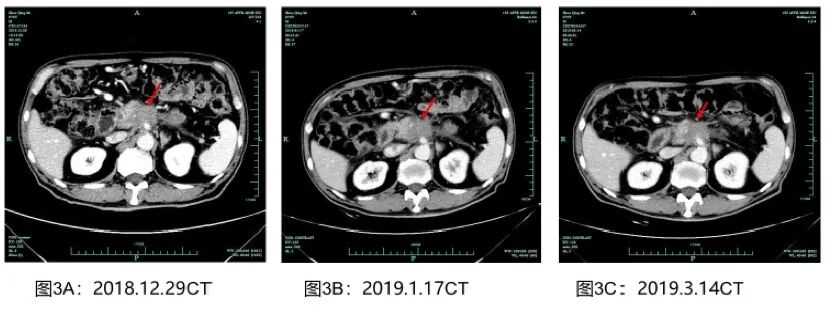

根据NCCN和CSCO指南,为患者选择AG方案进行一线治疗。考虑到患者高龄且基础疾病较多,因此对AG方案进行了剂量调整。患者于2019-1-18至2019-4-20接受改良AG方案一线治疗5个周期,具体药物和剂量为吉西他滨1000 mg/m2d1/8,q3w联合白蛋白紫杉醇140 mg/m2d1/8,q3w。该患者一线治疗获益较大,最佳疗效是PR。影像评估资料及肿瘤标志物情况如图3、图4所示。

图3 一线治疗影像评估(PR)